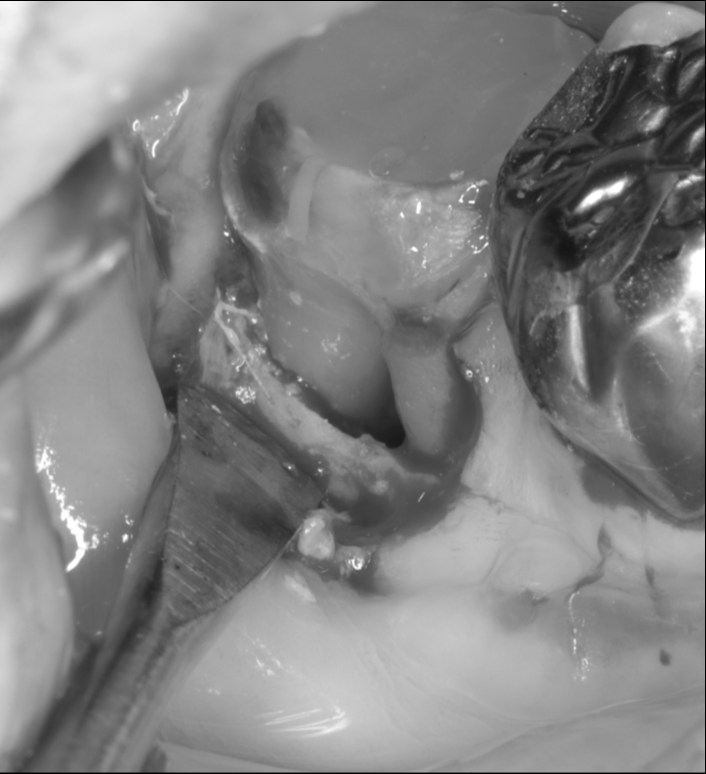

感染除去後

| 主訴 | 右奥歯から膿が出る 痛みが強い 歯を残したい |

| 治療内容 | 精密根管治療 歯周組織再生療法 セラミック修復 |